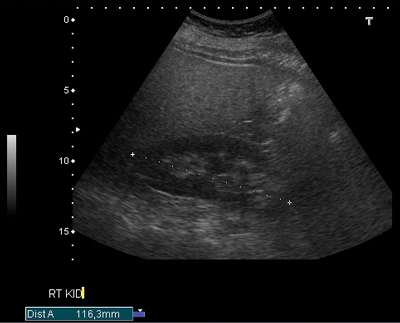

Figure 3a: US shows bar of cortex traversing the expected renal sinus fat.

Duplex kidney

Duplex kidney (Figure 3) has an incidence of 0.3-0.6% [8] and consists of two pelvicalyceal systems draining a single renal parenchyma. The two pelvicalyceal systems may have either a single or bifid ureter (partial duplication) or a double ureter draining each collecting system separately into the urinary bladder (complete duplication). In 20% the contralateral ureter is also duplicated. Complete duplication results in an ectopic ureter which inserts outside of the bladder trigone. Eighty-five percent of these ectopic ureters obey the Weigert-Meyer rule. This states the upper pole ureter inserts ectopically inferomedially to the orthostatic lower pole ureter, often with a ureterocoele.

The ureterocoele can cause obstruction of the upper moiety ureter, and also distort the orthostatic insertion of the lower moiety ureter causing reflux. In 15% of complete duplication cases, the upper moiety ureter inserts anywhere along the ectopic pathway [3]. In men, if this is outside of the bladder, the upper moiety ureter insertion is always above the external sphincter and so urinary continence remains, however in women the ectopic upper moiety ureteric insertion is below the sphincter, resulting in urinary incontinence. There is a heavy female predominance (M:F 1:10), which may also be due to the condition resulting in urinary incontinence in some women causing increased symptomatic presentation.

US is used for screening, and shows a band of renal parenchyma traversing the renal sinus fat. Two central echo complexes with intervening renal parenchyma demarcate the duplex system. However, US may fail to enable differentiation between a bifid renal pelvis from a bifid ureter or from two complete ureters [4]. The best imaging of the duplex system is shown on CT urogram which clearly demonstrates ureteric anatomy. On CT there are fewer calyces and infundibula of the lower moiety collecting system, and a shortened upper pole infundibulum. On axial slices the ‘faceless kidney’ sign can aid diagnosis, this is when no renal sinus or collecting system is seen at the junction of upper and lower pole of the duplex kidney [9].